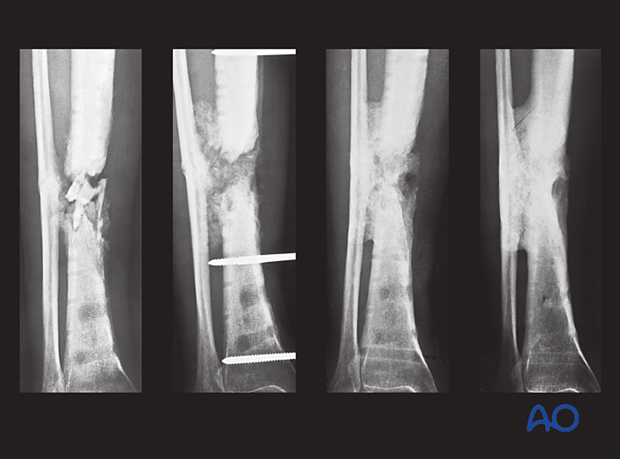

The image on the left shows a case of a young man, a Type B host, who required smoking cessation education when he had his original trauma. He developed a presumed aseptic hypertrophic nonunion of a diaphyseal tibia fracture that underwent IM nailing. The nail was removed, and a short segment of fibula was excised. The tibia was re-nailed after reaming to a larger diameter nail. The reamings were sent for culture and came back positive. Appropriate antibiotics were given for 6 weeks after surgery. The tibia healed without complication.